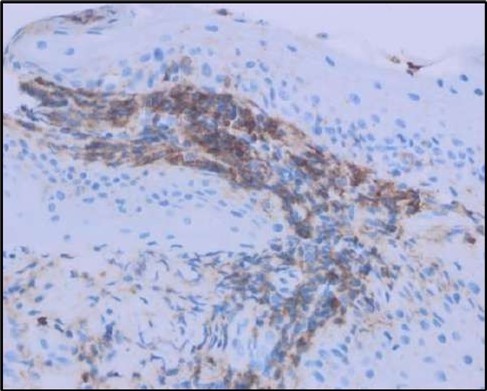

Figure 5c.OS, Immunohistochemical stain using CD45 (leukocyte common antigen) demonstrating a dense population of lymphocytes stained brown

Figure 5d.OS, Immunohistochemistry using CD138 showing many plasma cells (brown-stained) in the inflamed tissue.

Histopathological examination revealed a dense infiltration of CD138-positive plasma cells within the excised conjunctival tissue (Figure 5b, Figure 5c, Figure 5d). This finding supports an antibody-mediated immunopathogenesis in Mooren’s ulcer, consistent with Type II and Type III hypersensitivity mechanisms described in the literature 20, 21. The prominent presence of CD138- positive plasma cells provide a clear pathological rationale for conjunctival resection, as excision of the immunologically active perilimbal conjunctiva effectively removes the local 'factory' of autoantibodies that drive corneal stromal destruction, thereby halting ongoing tissue damage 21.